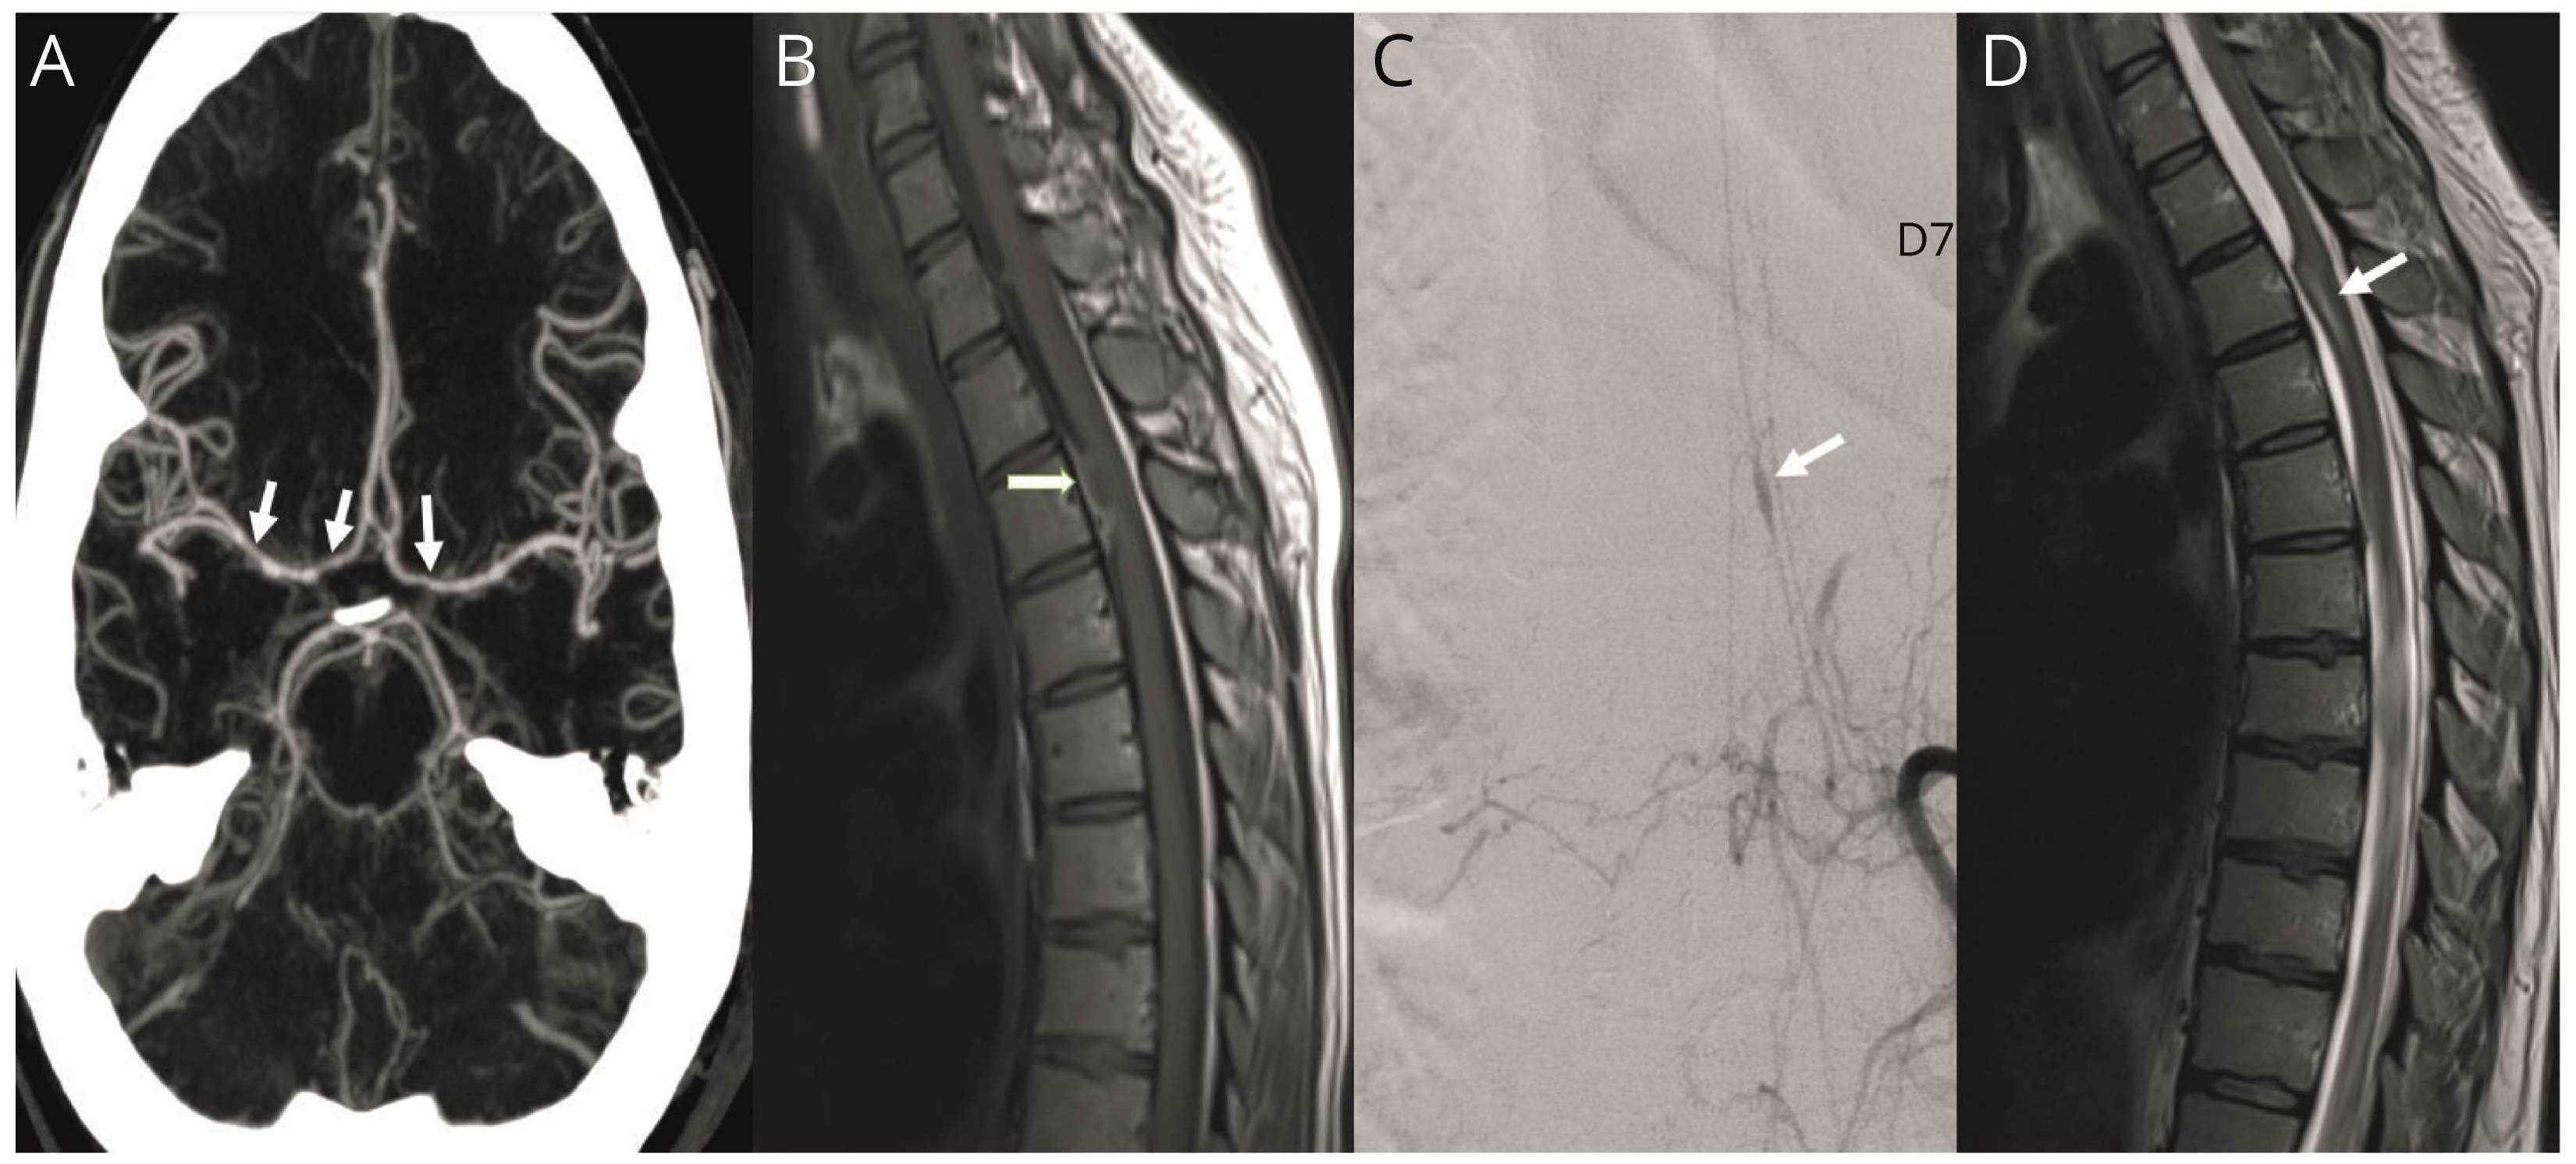

图2 CT血管造影和脊髓影像。

(A)产后第16天随访头颈部CTA显示颅内动脉弥漫性节段性狭窄,提示血管痉挛。(B)脊髓MRI T1序列显示T3水平不均一硬膜内髓外病变,伴脊髓受压,提示硬膜内血肿。(C)左侧T7动脉造影显示了Adamkiewicz动脉瘤。(D)3个月随访时T2序列显示T3水平蛛网膜粘连伴脊髓扭曲和继发性髓内信号变化。

括约肌功能障碍和双下肢感觉异常提示脊髓病变。脊柱MRI显示T1高信号,T2低信号,非增强性硬膜内髓外病变,考虑为血肿,提示脊髓SAH(图2-B)。硬膜外麻醉在该部位几个水平以下进行,无法解释血肿。脊柱血管造影显示T3和T7左根分支上存在两个梭状动脉瘤(图2-C)。

脊髓MRI显示T3水平存在T2高信号病灶和脊髓扭曲,以及多个部位粘连,提示蛛网膜炎(图2-D)。脊柱血管造影未见残留的动脉瘤。头颈部CTA证实血管痉挛消退,最初两个颅外椎动脉夹层正常化。该患者接受了手术以解决黏连,出院进行康复治疗。